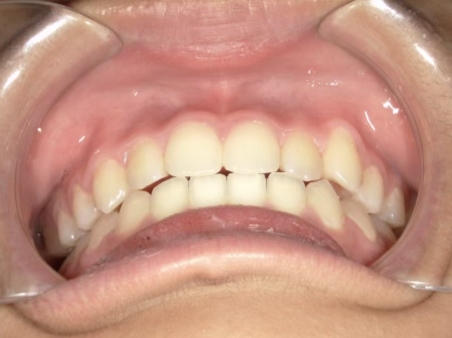

治療前① 小1:6y8m 初診

| カウンセリング・診断結果 | 前歯の生え変わり時期に来院されました。(写真①) 乳歯列期に受け口の既往があり切端咬合になりそうなため、受け口に対する矯正治療の考え方と対処法、当院のコンセプトを説明したところ治療を希望されたので診断を行いました。 診断の結果、上顎骨に対し下顎骨が長く、骨格的な構造も下顎突出型反対咬合(下顎骨が適切な位置よりも前に出ているタイプの受け口)と分かりました。 顔立ちは、中顔面が引っ込んだように見えるコンケーブに移行中です。 機能的な問題として低位舌があるため受け口の悪化が考えられることも説明し、以下の治療を提案しました。 |